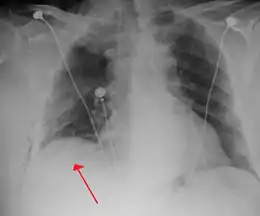

Chest X-ray

A plain chest radiograph, ideally with the X-ray beams being projected from the back (posteroanterior, or "PA"), and during maximal inspiration (holding one's breath), is the most appropriate first investigation.[30] It is not believed that routinely taking images during expiration would confer any benefit.[31] Still, they may be useful in the detection of a pneumothorax when clinical suspicion is high but yet an inspiratory radiograph appears normal.[32] Also, if the PA X-ray does not show a pneumothorax but there is a strong suspicion of one, lateral X-rays (with beams projecting from the side) may be performed, but this is not routine practice.[15][19]

Anteroposterior inspired X-ray, showing subtle left-sided pneumothorax caused by port insertion

Lateral inspired X-ray at the same time, more clearly showing the pneumothorax posteriorly in this case

Anteroposterior expired X-ray at the same time, more clearly showing the pneumothorax in this case

It is not unusual for the mediastinum (the structure between the lungs that contains the heart, great blood vessels, and large airways) to be shifted away from the affected lung due to the pressure differences. This is not equivalent to a tension pneumothorax, which is determined mainly by the constellation of symptoms, hypoxia, and shock.[13]

The size of the pneumothorax (i.e. the volume of air in the pleural space) can be determined with a reasonable degree of accuracy by measuring the distance between the chest wall and the lung. This is relevant to treatment, as smaller pneumothoraces may be managed differently. An air rim of 2 cm means that the pneumothorax occupies about 50% of the hemithorax.[15] British professional guidelines have traditionally stated that the measurement should be performed at the level of the hilum (where blood vessels and airways enter the lung) with 2 cm as the cutoff,[15] while American guidelines state that the measurement should be done at the apex (top) of the lung with 3 cm differentiating between a "small" and a "large" pneumothorax.[33] The latter method may overestimate the size of a pneumothorax if it is located mainly at the apex, which is a common occurrence.[15] The various methods correlate poorly but are the best easily available ways of estimating pneumothorax size.[15][19] CT scanning (see below) can provide a more accurate determination of the size of the pneumothorax, but its routine use in this setting is not recommended.[33]

Not all pneumothoraces are uniform; some only form a pocket of air in a particular place in the chest.[15] Small amounts of fluid may be noted on the chest X-ray (hydropneumothorax); this may be blood (hemopneumothorax).[13] In some cases, the only significant abnormality may be the "deep sulcus sign", in which the normally small space between the chest wall and the diaphragm appears enlarged due to the abnormal presence of fluid.[16]